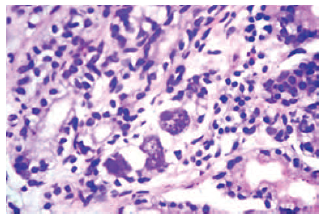

In June 2012, a gastrointestinal endoscopy was repeated, which showed linear erosions in the distal body and the antrum of the stomach, associated with ulcerations. A biopsy specimen showed mildly edematous lamina propria with lymphocytic infiltrates. Multiple CMV inclusions, both cytoplasmic and intranuclear, were seen in the gastric glands. Immunohistochemical staining with CMV specific-labeled antibody was positive (Figures 1 and 2). A diagnosis of CMV gastritis was made. The patient’s CMV viral load in the blood by polymerase chain reaction (PCR) was below the detectable limit. The patient’s MMF was stopped, and she was treated with intravenous ganciclovir 2.5 mg/kg/day (according to the estimated glomerular filtration rate) for 21 days, followed by oral valganciclovir for 3 months. After beginning this therapy, her symptoms began to improve in 10 to 15 days. She did not tolerate the ganciclovir well, and this therapy had to be stopped twice because of leucopoenia that required administration of granulocyte colony-stimulating factor. The results of a repeat gastric biopsy showed healing of the lesions with an absence of inclusions on histopathology.

Figure 1. Gastric Biopsy Showing Cytomegalovirus Inclusion Body in the Cell of Gastric Gland (H&E Stain)

Figure 2. Immunohistochemistry Showing Cytomegalovirus Inclusion Body